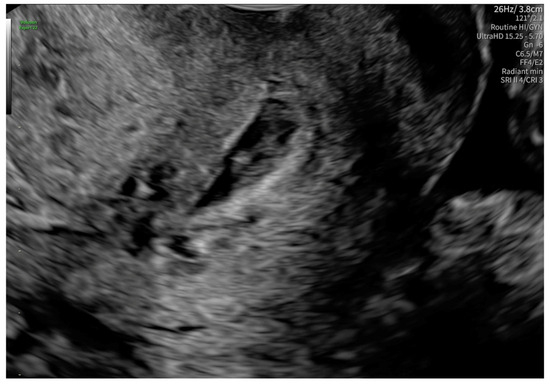

2. Case Presentation